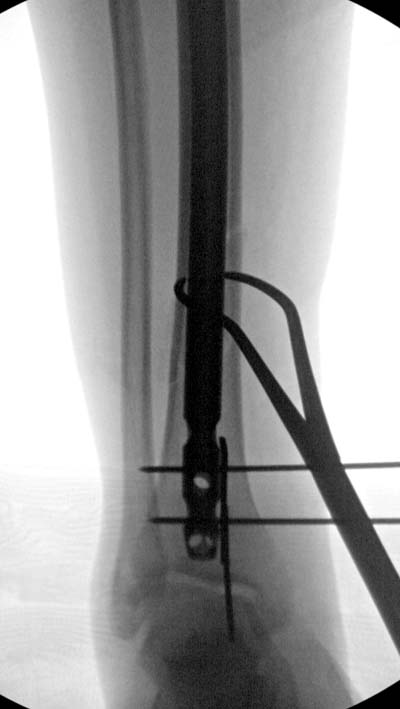

Здесь несколько снимков изолированного перелома большеберцовой с

интактной малоберцовой.  Weber clamp, блокирующие спицы и риминг в

центре канала отрепонировал перелом....